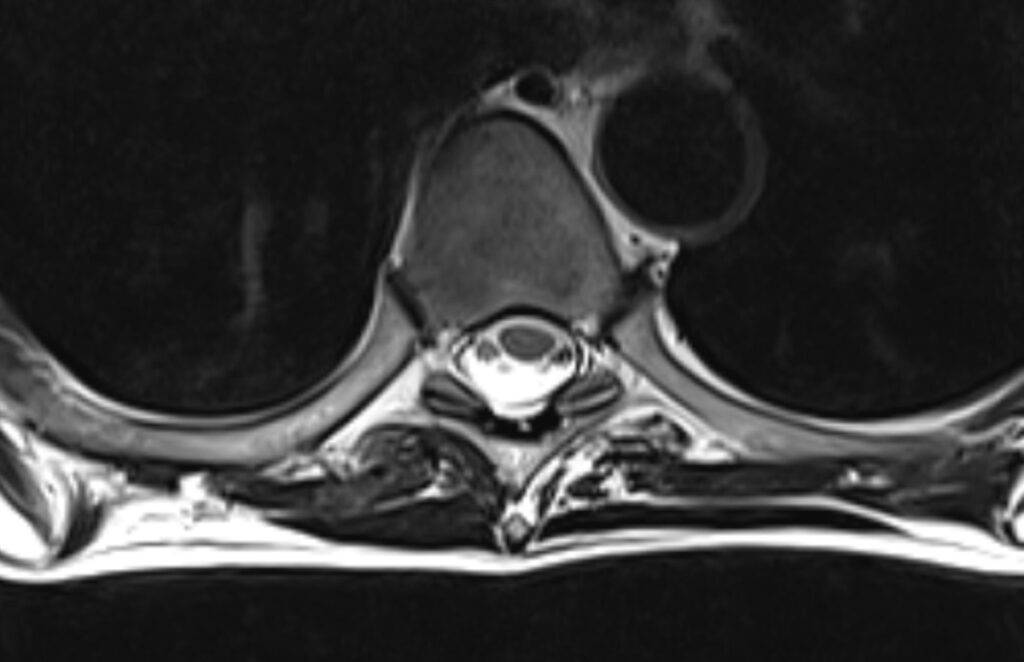

Bei einer Wirbelsäule MRT können sowohl knöcherne Strukturen als auch Weichteile erkannt und folglich untersucht werden. Dadurch eignet sich die MRT Wirbelsäule besonders gut, um Schmerzen mit unklarer Ursache im Rücken und der Wirbelsäule abzuklären. Denn auf den MRT-Bildern des Rückens können Schäden an der Wirbelsäule, den Bandscheiben und am Rückenmark erfasst werden.

Mögliche Erkrankungen an diesen Strukturen sind mit der nicht-invasiven bildgebenden Methode, wie es die Kernspintomographie bzw. Magnetresonanztomographie ist, bereits in frühen Stadien erkennbar, was für viele Patienten die Aussichten auf eine erfolgreiche Therapie erhöht bzw. die Prognose verbessert.

- Bandscheibenvorfall